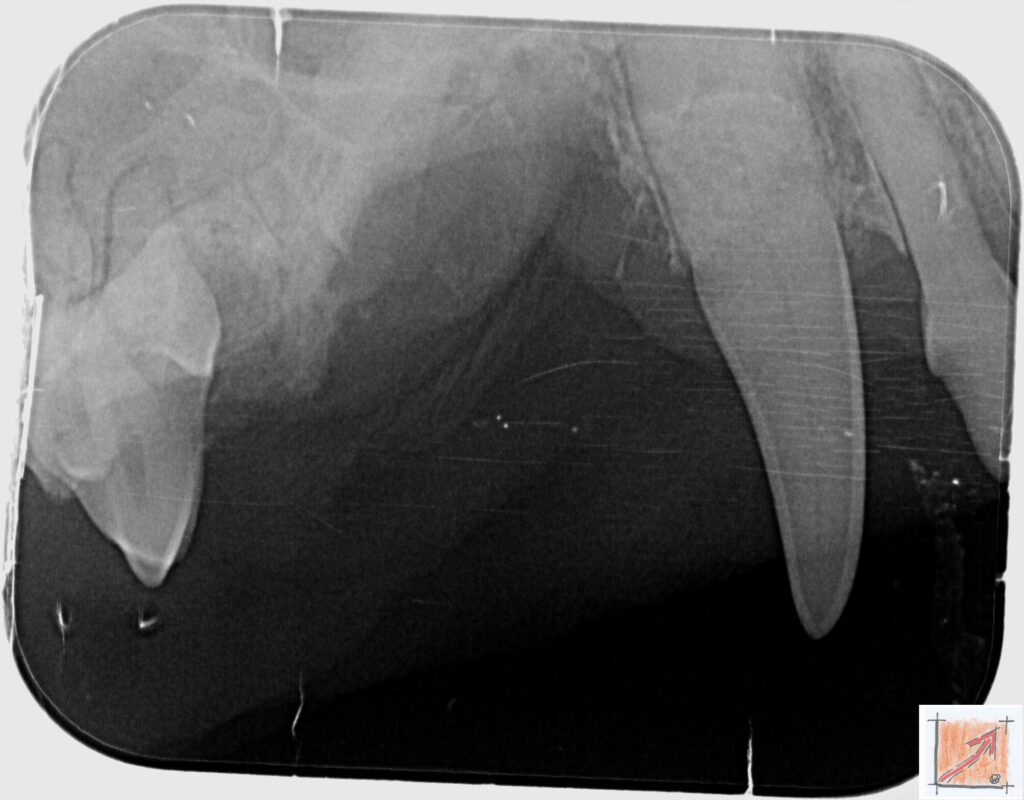

Röntgenbilder vom Thierrischen Orakel bei der Zahn-OP:

Warum Dentalröntgen beim Chihuahua lebenswichtig ist:

Ein Blick hinter die Kulissen von Chihuahua-Zähnen:

In dieser Galerie zeigen wir exklusive intraorale Röntgenaufnahmen einer Zahn-Operation beim Thierrischen Orakel als Chihuahua vom BauFachForum. Während oberflächlicher Zahnstein oft sichtbar ist, verbirgt sich die wahre Gefahr für das Herz meist unter dem Zahnfleischsaum.

Das digitale Dentalröntgen ist der Goldstandard in der modernen Tiermedizin, um parodontale Entzündungsherde und Wurzelabszesse sicher zu diagnostizieren. Für Chihuahuas wie dem Thierrischen Orakel, mit Mitralklappeninsuffizienz ist dieser diagnostische Schritt essenziell. Nur wenn versteckte Bakterienherde an der Zahnwurzel oder mit dem Fachbegriff Apikalabszesse erkannt und saniert werden, kann das Risiko einer bakteriellen Endokarditis oder einfach ausgedrückt einer Herzinnenhautentzündung minimiert werden.

Unsere Aufnahmen von Patienten dem Thierrischen Orakel verdeutlichen den Unterschied zwischen einer rein optischen Zahnreinigung und einer medizinisch fundierten Sanierung unter Röntgenkontrolle.

Chihuahua Mitralklappeninsuffizienz Trachealkollaps:

Wichtig ist im Vorfeld die Zahnhygiene des Chihuahuas. Die Bilder zeigen Dentale Röntgenbilder vom Thierrischen Orakel als Chihuahua-Hund während seiner Zahn-OP. Darstellung von Kieferknochen und Zahnwurzeln zur Diagnose von Parodontitis.

Zahnröntgenaufnahme bei Chihuahua Thierry:

Untersuchung der Zahnwurzeln auf Entzündungsherde als Prophylaxe gegen bakterielle Endokarditis.

Intraorales Dentalröntgen eines Chihuahuas:

Die Bilder zeigen Zähne und Wurzelstrukturen im Unterkiefer zur Planung einer Extraktion bei hochgradigem Zahnstein.